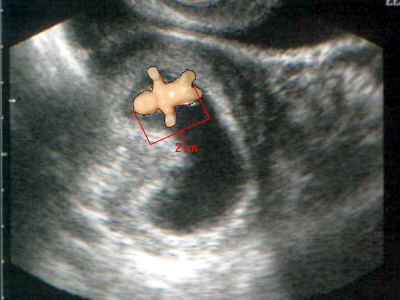

Эмбрион 6 7 Недель ФотоВыберите Ваш пол👨 👉🏻👉🏻👉🏻МУЖЧИНА👈🏻👈🏻👈🏻👩🦱 👉🏻👉🏻👉🏻ЖЕНЩИНА👈🏻👈🏻👈🏻Эмбрион 6 7 Недель Фото (132 фото)